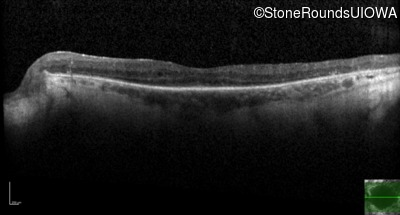

Optical Coherence Tomography - Left - 20/40 +1

Exemplar / OCT Stack

OCT Stack